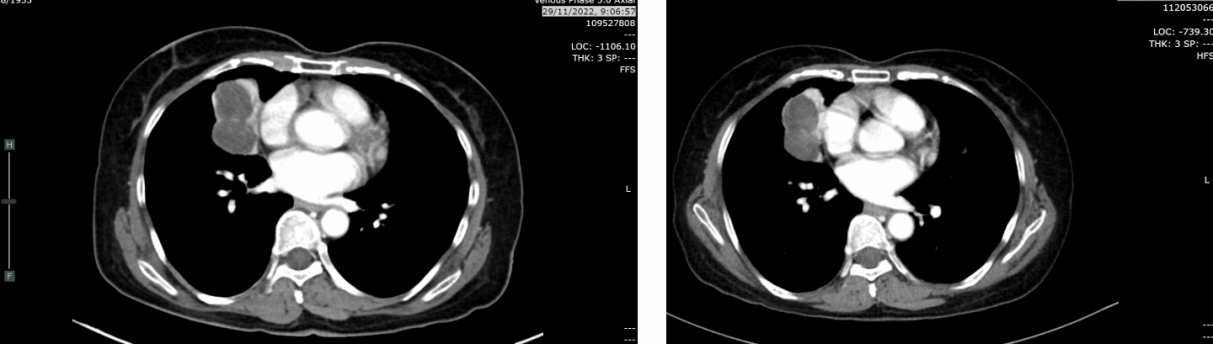

复查CT(2023-12-19):CT示肿块轻度增大至4.1cm(较7月增长24%),右肺上、中、下叶新见牵拉性支气管扩张及实变影,鉴别诊断包括浸润性转移、感染或混合性肺不张/实变。无肝、肾上腺、淋巴结或骨转移。

2024年3月21日:肿块缩小至2.8cm,实变及结节较前减少,考虑肺转移灶部分消退。

2024年6月17日:肿块略增至2.9cm,亚厘米级淋巴结。

2025年8月26日:肿块2.2cm,右肺上叶、中叶结节0.3-0.4cm稳定,中叶新增磨玻璃影(考虑感染或炎症),无新增转移灶。